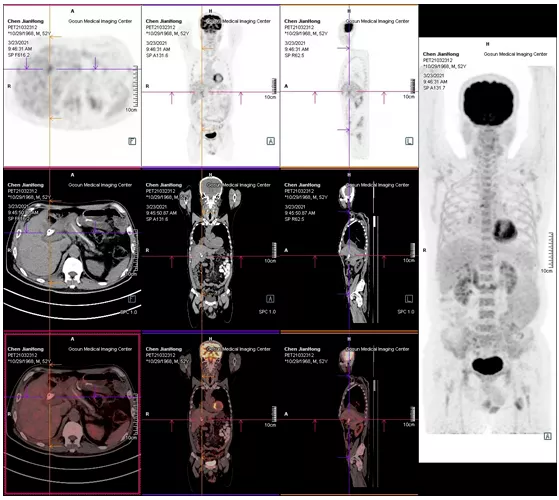

06

2021年05月 PET/CT檢查結(jié)果

復查PET-CT提示原術(shù)區(qū)復發(fā)病灶、肝內(nèi)轉(zhuǎn)移灶、右側(cè)胸膜轉(zhuǎn)移灶控制良好

image.png

治療效果評估

用藥3個月后,患者精神狀態(tài)明顯好轉(zhuǎn),食欲改善,體重增加,腫瘤指標下降,PET/CT結(jié)果提示,無明顯腫瘤復發(fā)或轉(zhuǎn)移征象,肝內(nèi)腫瘤活性已受抑制。